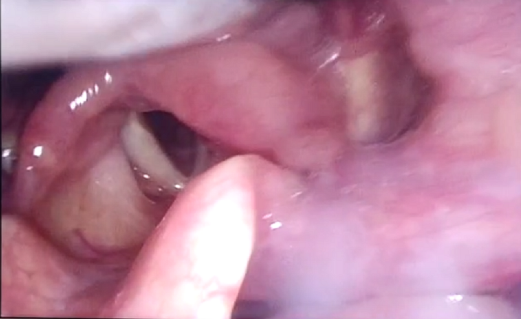

经康复科吞咽康复系统治疗后,程阿姨吞咽功能明显改善,颜面口肌功能得到较大提高,舌各向抗阻,咽反射均较前好转。近日,在给患者吞咽特调的绿染中稠流质食物和绿染液体各3ml和5ml后,观察到患者吞咽启动可,会厌谷、梨状窦无染色食物残留,无渗漏,无误吸,无呛咳,即治疗一疗程后,吞咽功能明显改善,在能经口保证足够营养摄入的情况下,建议可拔除鼻饲管,提高了程阿姨的生活质量。

图为吞食绿染液体后,喉内镜下显示,会厌谷、梨状窦无绿染色液体残留,无渗漏,无误吸。